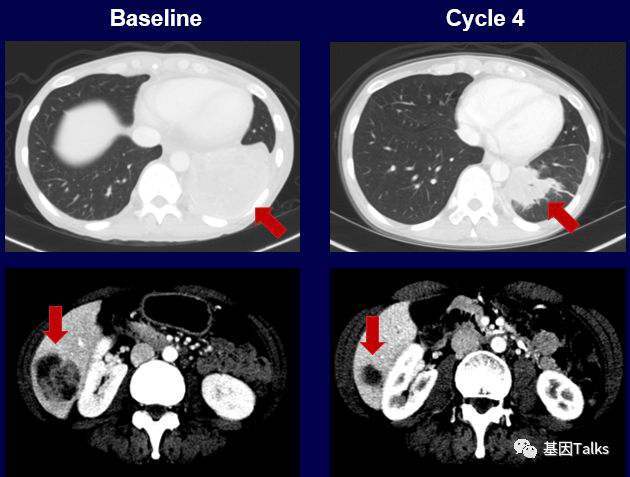

三个不同癌种不同融合的案例:

(1)1例肺癌合并SQSTM1-NTRK1融合:

(2)1例婴儿纤维肉瘤合并ETV6-NTRK3融合:

(3)1例分泌性乳腺癌合并ETV6-NTRK3融合:

上图下半部分显示治疗2周后,新发的耐药突变位点G595R已经检测不到,到目前治疗已经6个月了,治疗效果依然很好,未见有新的耐药位点出现。LOXO-195已经被FDA批准正式开展临床试验,耐药患者有了新希望。